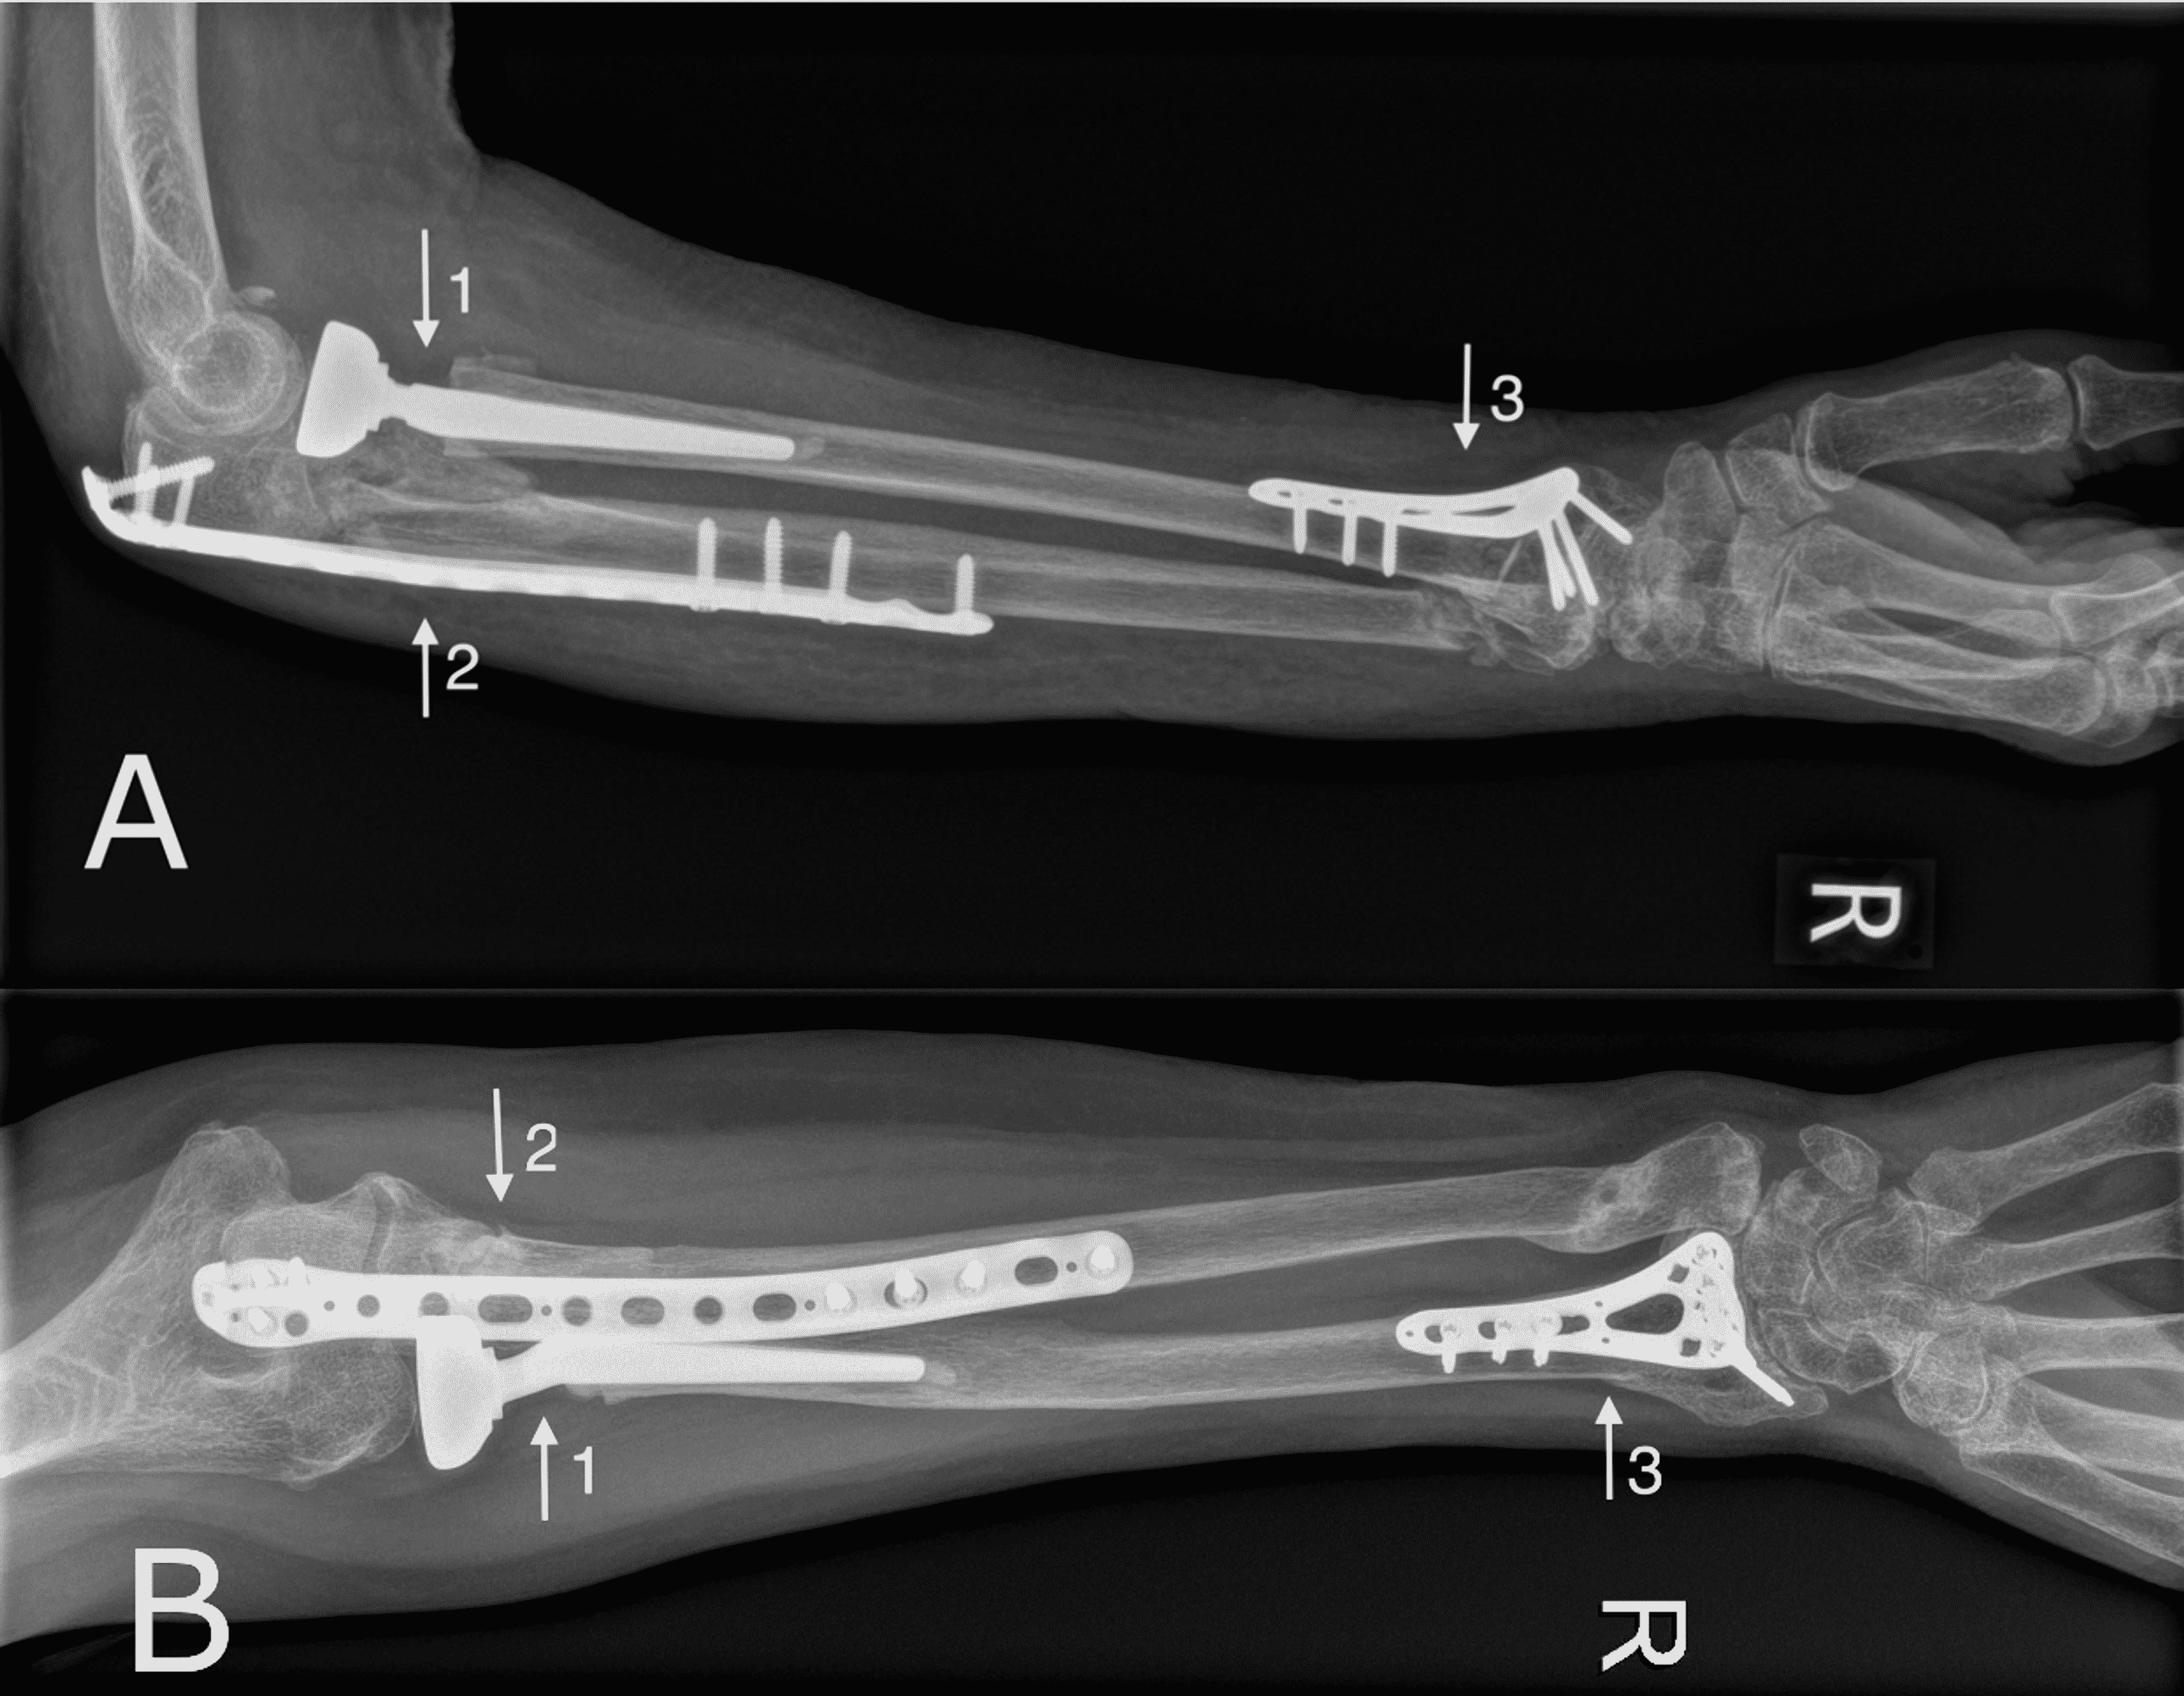

From jtojournal.com

Monteggia Fracture Dislocation with Ipsilateral Distal Radius Ulna Radius And Ulna Fracture Complications In Child An isolated ulna fracture may be. Pediatric radius and ulna fractures. Most common fractures seen in pediatric patients; Forearm fractures are common in childhood, accounting for more. The radius and the ulna. Both bones in the forearm are affected. It is made up of two bones: There are six types of forearm fractures in children: In most cases, the radius. Radius And Ulna Fracture Complications In Child.